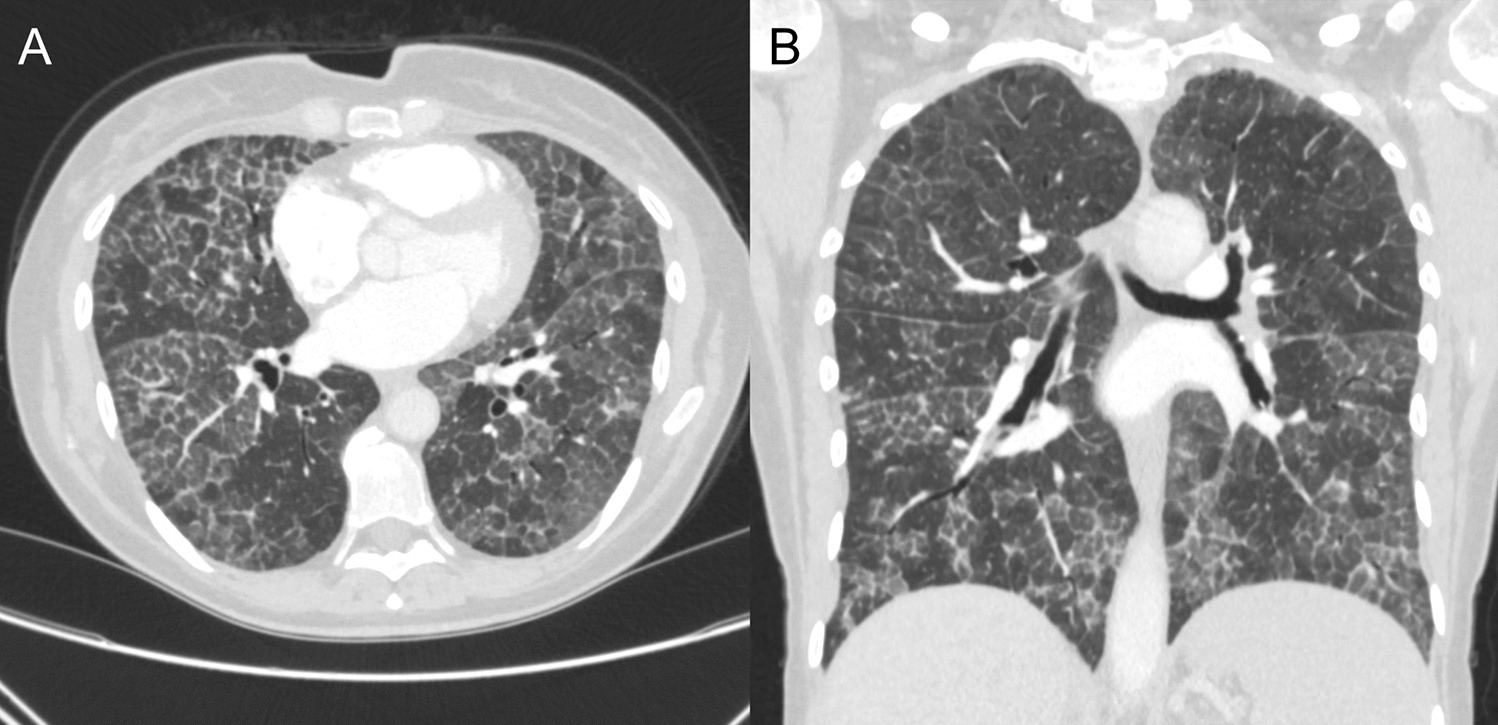

Cystic Lung Diseases: A Radiology Primer

Cystic Lung Diseases (CLD) represent a diverse group of lung diseases characterized by the presence of intraparenchymal cy...

Diffuse Cystic Lung Disease – Updates and Opportunities for Advancement

To provide an updated, comprehensive overview of diffuse cystic lung diseases (DCLDs), highlighting diagnostic and therape...